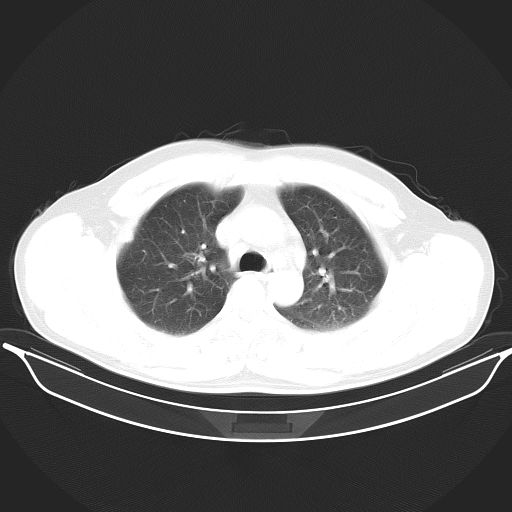

标题: CT25490:男,40岁,体检发现;无其它不适。 [打印本页]

标题: CT25490:男,40岁,体检发现;无其它不适。

考虑右下肺周围性肺癌并肺内多发转移,纵隔淋巴结转移!

支持 !考虑右下肺周围性肺癌并肺内多发转移,纵隔淋巴结转移,(气管前腔静脉后,隆突下,主动脉弓下都有了)